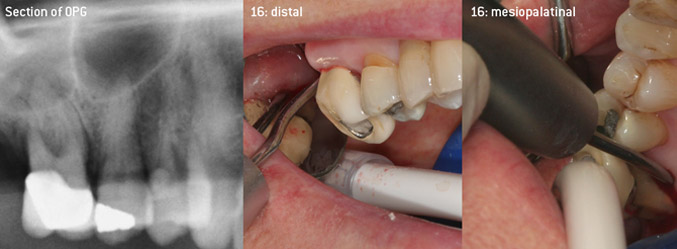

The aim was to develop a universally applicable tip in order to avoid time-consuming tip changes. In addition, it should be easier to use the new working tips in tight intraosseous pockets from distal and at the distal furcation entrance of maxillary molars, allowing more effective use of instruments as a result. This was achieved by employing an instrument curve with a larger diameter (Figure 1), which is highly advantageous for closed debridement on teeth with advanced attachment loss and involvement of furcation in particular (Figure 4).

Closed debridement of the furcation on tooth 16

Fig. 4: Closed debridement of the furcation on tooth 16 with advanced attachment loss